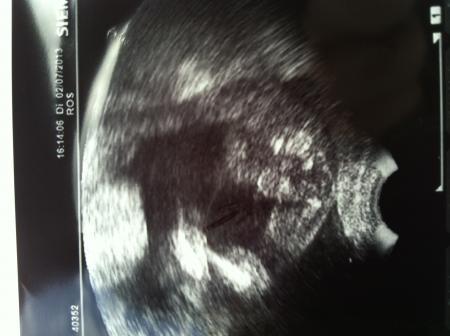

War heut mittag bei meiner FÄ und sie meinte, heute hören wir nur mal nach den Herztönen und schauen nach dem Muttermund und dem Gebärmutterhals. Da war ich schon total enttäuscht, wieder kein Outing. Sie hat dann nach dem Gebärmutterhals geschaut und dabei gesehen, das unser kleiner Zwerg in SL lag, dann hat sie mal genauer versucht zwischen die Beinchen zu schauen und........... da war es, es wird ein Junge! Sonst war auch alles okay, einen kräftigen Herzschlag hätte unser Krümel, meinte sie. Dann kam das neueste, bekomm am Donnerstag Organscreening, muss dafür 140€ in Vorkasse gehen, bekäme es aber von der KK wieder zurück Da bin ich mal gespannt, ob ich das wirklich wieder bekomm, aber die hauptsache ist, das ich schon am Donnerstag meinen kleinen Zwerg wieder sehen kann und das dabei alles in Ordnung ist!

hier noch das Beweisfoto...